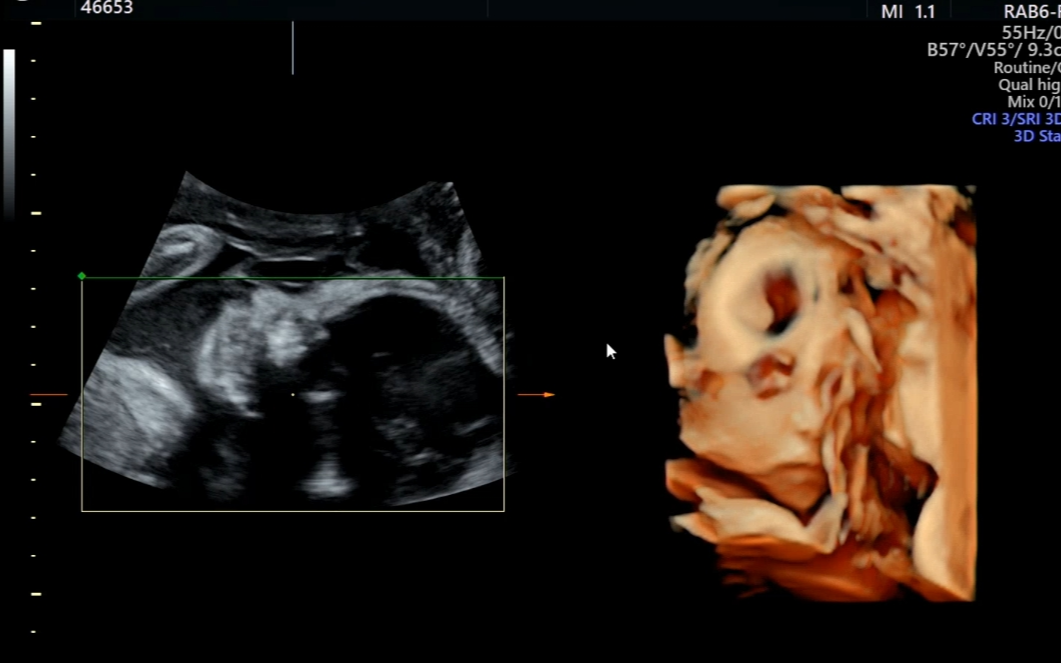

병원 도착 후 시간이 남아 먼저 초음파를 봤다.

정밀초음파 이후 4주 만인데 꿀떡이는 역시나 머리와 배 둘레 모두 주수보다 1주 이상 크게 자라고 있었다.

건강하게 자라고 있다는 말에 한시름 놓였다.

선생님이 입체초음파로 얼굴을 보여주려 했지만 탯줄에 가려 잘 보이지 않았고,

결국 뒤돌아 누운 꿀떡이의 뒤통수만 보다가 끝났다.

그래도 찍힌 얼굴 사진을 보니 신기하고 묘했다.

아직 볼살이 없어 그런지 어른 얼굴 같기도 했다. 4주 뒤 너의 모습이 기대되는구나!